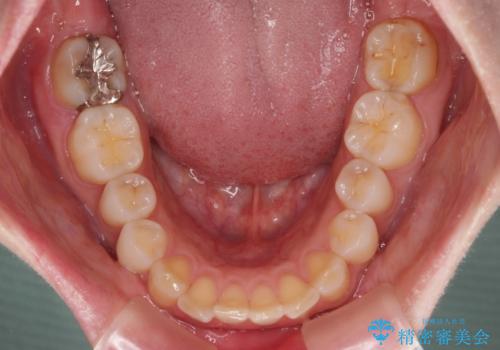

- 上の前歯が出っ歯と突出した口元を気にして来院された患者様です。

上顎歯列全体が前方に飛び出している印象であったので、上顎左右の第一小臼歯2本を抜歯し、ワイヤー装置にて抜歯矯正を行うこととしました。

骨格的に上顎が前方にあり、上顎のみの抜歯矯正のため、期間はかかることが予想されましたが、スムーズに移動してくれたおかげで、2年弱の短期間で終えることができました。